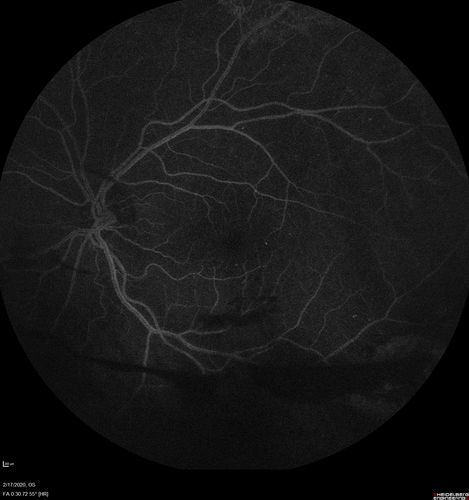

PDR and Vitreous Hemorrhage - High Risk Left Eye - Low Risk Right Eye

50 year old man with type I diabetes mellitus for 26 years. New Vitreous Hemorrhage in the left eye. Both eyes have NVE. Both also have foveal hypoplasia

Vitreous Hemorrhage and Proliferative Diabetic Retinopathy - Low risk right eye - High Risk Left Eye - Also Fovea Plana